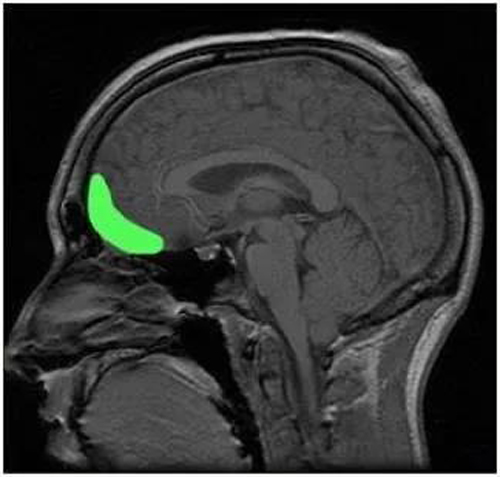

抑郁症病人大脑的海马体体积比没有抑郁症的人明显更小。

海马体是我们大脑中非常重要的一个区域,它负责着记忆、认知区域以及一些情绪功能。而它的萎缩也代表着人类大脑记忆力的衰退、认知的下降以及情绪的抑郁。

【正常大脑(左)与抑郁症患者大脑(右)海马体大小对比】

一旦抑郁得不到及时的治疗,抑郁的状态持续过久,大脑海马体的体积就会变得越来越小,反之若得到及时治疗,海马体的体积则会有所恢复。